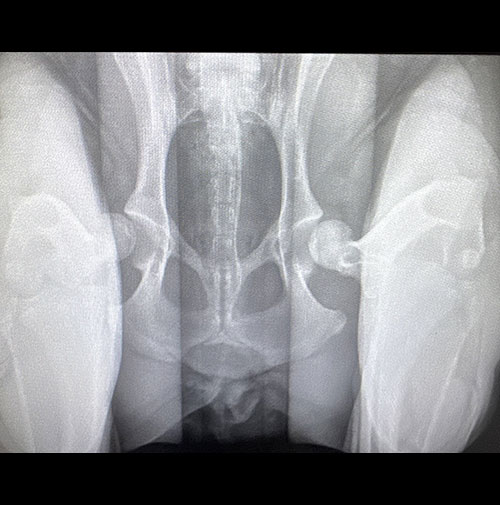

While humans generally develop primary arthritis, dogs actually get secondary osteoarthritis – arthritis that forms due to an underlying orthopedic problem. Conditions like hip dysplasia, elbow dysplasia, or cruciate ligament injuries can damage a joint early in life, setting the stage for joint degeneration and years of pain.

A recent study1 published in 2024 found that 40% of dogs under four years old already have evidence of osteoarthritis on X-rays in at least one joint. More than 30% of dogs had arthritis in at least two or more joints.

In that same study, only about one quarter of the dogs with arthritis visible on x-rays showed obvious signs of pain during a veterinary exam. And even when they did show signs of pain, owners only recognized those signs about 30% of the time.